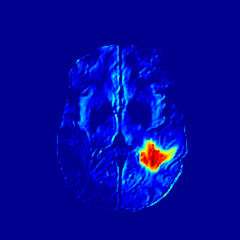

IV-D Results on more MRI modalities with brain tumor.

The ANT-GAN model is mainly evaluated and validated on the FLAIR modality. However, we also test the ANT-GAN model on other three MRI setting including T2, T1ce and T1 modalities. The generated pseudo healthy images are shown in Figure 10.

Refer to caption

Figure 10: More results on the synthesized normal-looking MRI images on T1ce, T2 and T1 modalities.